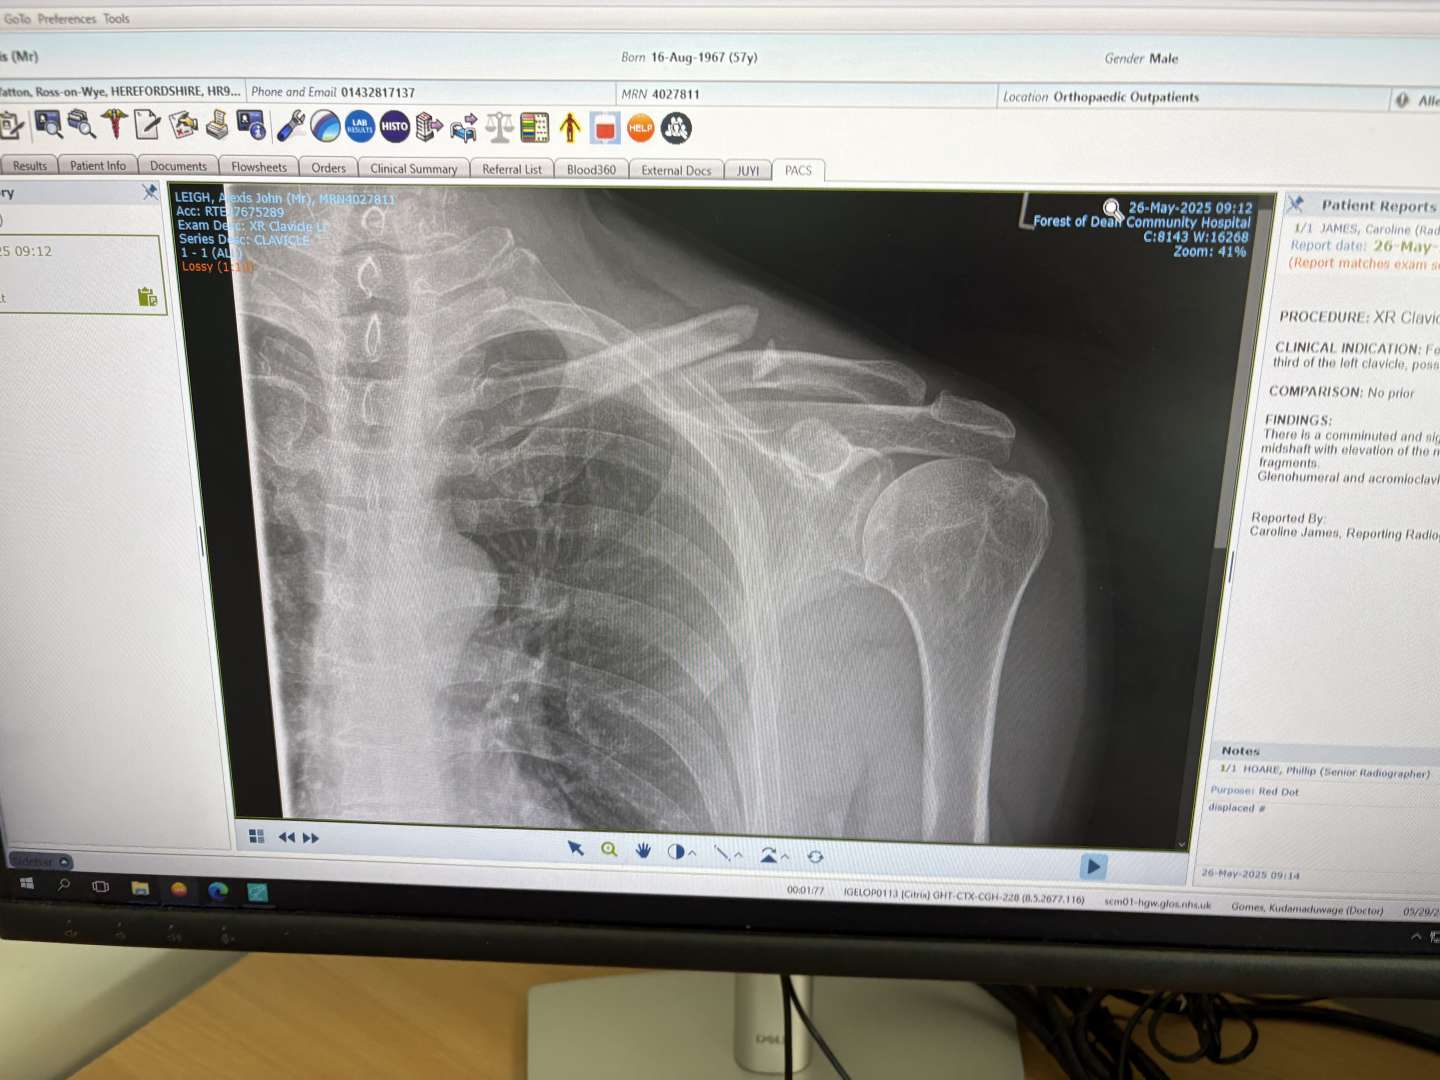

So I went to fracture clinic. Consultant and another doc. Absolutely zero interest in plating it as bone not pushing through skin. View was it would rejoin - I look at that xray and think "Really?". Anyway back in three weeks, if it's not healing they'll plate it.